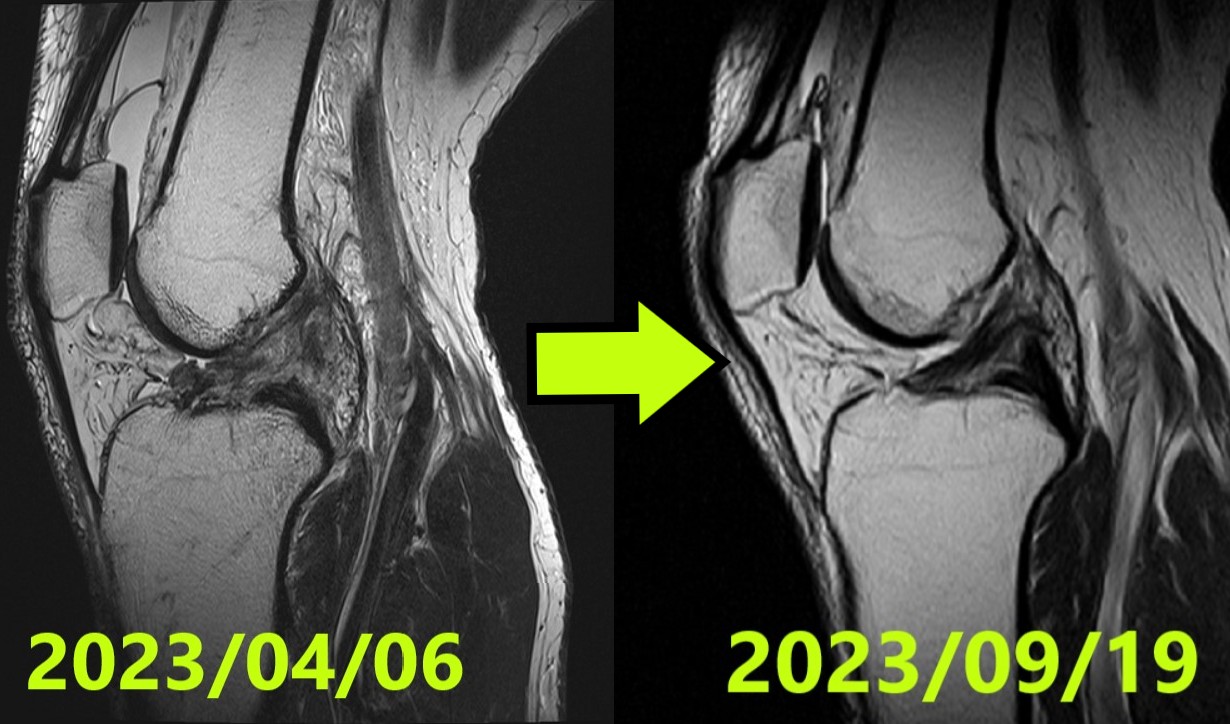

前十字韌帶自然癒合病例報告 #53:雖然臨床表現穩定但自然癒合失敗,最終選擇手術治療之案例(13 歲日本女性)

病例 50 | 前十字韌帶自然癒合:從最嚴重的 Ihara IV 型到完美的正常結構再生 (ACLOAS 0)

前十字韌帶自然癒合病例報告 #50:最嚴重的 Ihara IV 型完全斷裂成功再生至 ACLOAS 0 型之最…